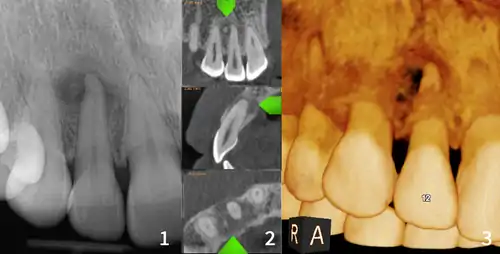

Florid osseous dysplasia of the mandible | |

Diagnostic method | X-ray, CBCT scan, vitality testing of teeth |

Cemento-osseous dysplasia (COD) is a benign condition of the jaws that may arise from the fibroblasts of the periodontal ligaments. It is most common in African-American females. The three types are periapical cemental dysplasia (common in those of African descent), focal cemento-osseous dysplasia (Caucasians), and florid cemento-osseous dysplasia (African descent). Periapical occurs most commonly in the mandibular anterior teeth while focal appears predominantly in the mandibular posterior teeth and florid in both maxilla and mandible in multiple quadrants.

Diagnosis is important so that the treating doctor does not confuse it for another periapical disease such as rarefying osteitis or condensing osteitis. Incorrect diagnosis could lead to unnecessary root canal treatments. It can be diagnosed by radiographic appearance. Confirming the tooth is vital, as is noting the demographic (African American females).[1][2][3]